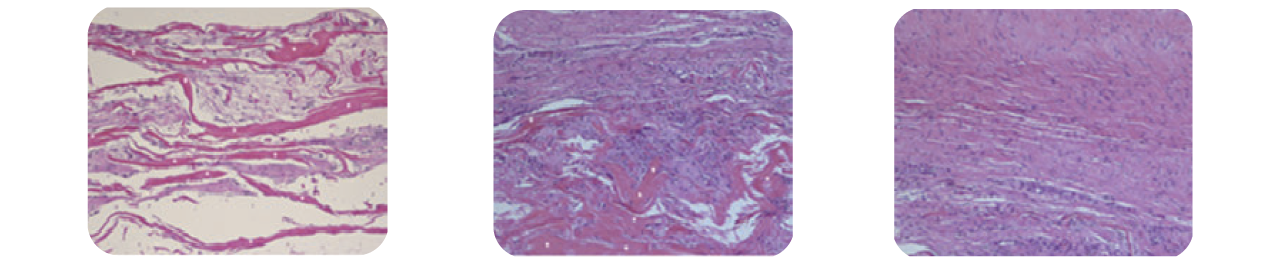

5 週でインプラントの間隙内に宿主細胞( 線維芽細 胞) の

存在が認められ、初期のコラーゲン形成が確認出来た。

インプラントの残存ははっきり確認出来る(※)

3 か月でインプラントへのコラーゲンの

形成・成熟 ・配向の増加が示された。

コラーゲンインプラントは残存が確認出来る(※)

6 か月で新生組織は腱の組織学的外観を示し、

新生宿主組織の負荷機能を示唆した。

コラーゲンインプラントの残存は無かった